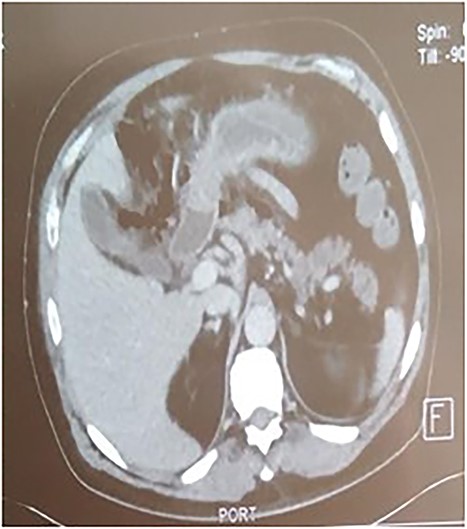

A 53-year-old man with no known medical history was admitted to the hospital because of epigastric pain persisting for 24 h, accompanied by weakness. Physical examination revealed a temperature of 39°C, severe dehydration, poor peripheral perfusion, a pulse of 110 bpm, blood pressure at 10/6 mm/Hg, a painful and tympanic abdomen without peristalsis, with tenderness over the epigastric region. Laboratory tests showed a lipase level of 667 U/l, sodium at 140 mmol/l, potassium at 4.5 mmol/l, creatinine at 106 μmol/l, urea at 6.5 mmol/l, alanine aminotransferase at 161 U/l, aspartate aminotransferase at 85 U/l, an elevated leukocyte count at 29,3 × 109/l. Abdominal CT with contrast revealed pancreatic necrosis with gas surrounding the pancreas, as well as pneumoperitoneum and in the right anterior pararenal space. Thickening of the mesentery root with lymph node enlargement (Figs 1–3).

The patient was treated with fluids, imipenem, and underwent emergency surgery. Laparotomy showed purulent fluid in the peritoneal cavity with diffuse gangrene involving the distal small bowel and the right colon. The mesentery root was markedly thickened and infiltrated, site of multiple purulent collections. Gangrene was present in the omental bursa with destruction of the cephalic part of the pancreas. The procedure included necrosectomy extensive cleansing, right colectomy with double ileostomy and colostomy, and drainage (Figs 4 and 5). Unfortunately, the patient succumbed to septic shock a few hours after the intervention. The purulent fluid sample returned after examination and culture positive to C. perfringens.